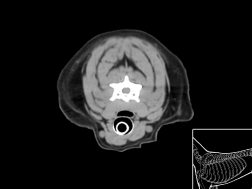

Atlas cérébral du chien SCTM

Scanner tissu mou

>> 30 coupes